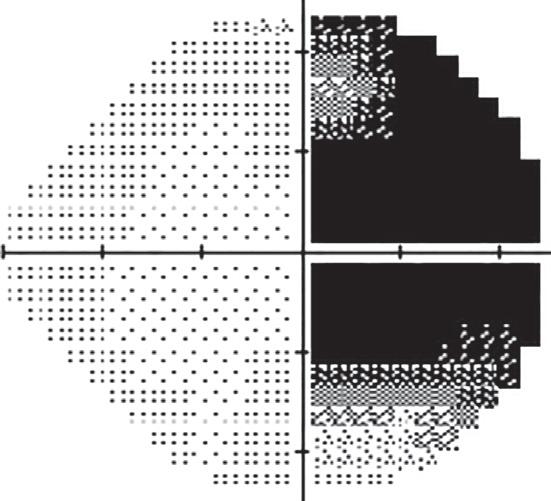

1.2 This 16-year-old girl presented to the ophthalmology department complaining of headaches, blurred vision in her right eye and flashing lights. Visual acuity was 20/20 in each eye and intraocular examination was normal. No visual field testing was performed, and the patient was told her symptoms were due to migraine. Re-examination by another doctor revealed a right homonymous hemianopia (A, B) that was easily detected with confrontation testing; C a left thalamic mass lesion was diagnosed on MRI; further investigation showed this to be a cryptococcal abscess.

1.5 Not all chronic optic neuropathy with a “cupped” disc is glaucoma! This 48-year-old patient asked her optometrist for a change of glasses because of blurred vision. The optometrist found A, B visual acuity right 20/30, left 20/60, intraocular pressures of right 25, left 29, and bilateral disc “cupping”, and referred the patient to an ophthalmologist for treatment of possible glaucoma. Perimetry was attempted but fields were said to be “unreliable”; the ophthalmologist commenced glaucoma eyedrops. One year later, visual acuity had decreased further to right 20/60, left 20/200, and optic disc pallor was noted; C MRI revealed a large suprasellar meningioma. Visual outcome would probably have been better with earlier diagnosis. For how to safely diagnose glaucoma, see p. 37.